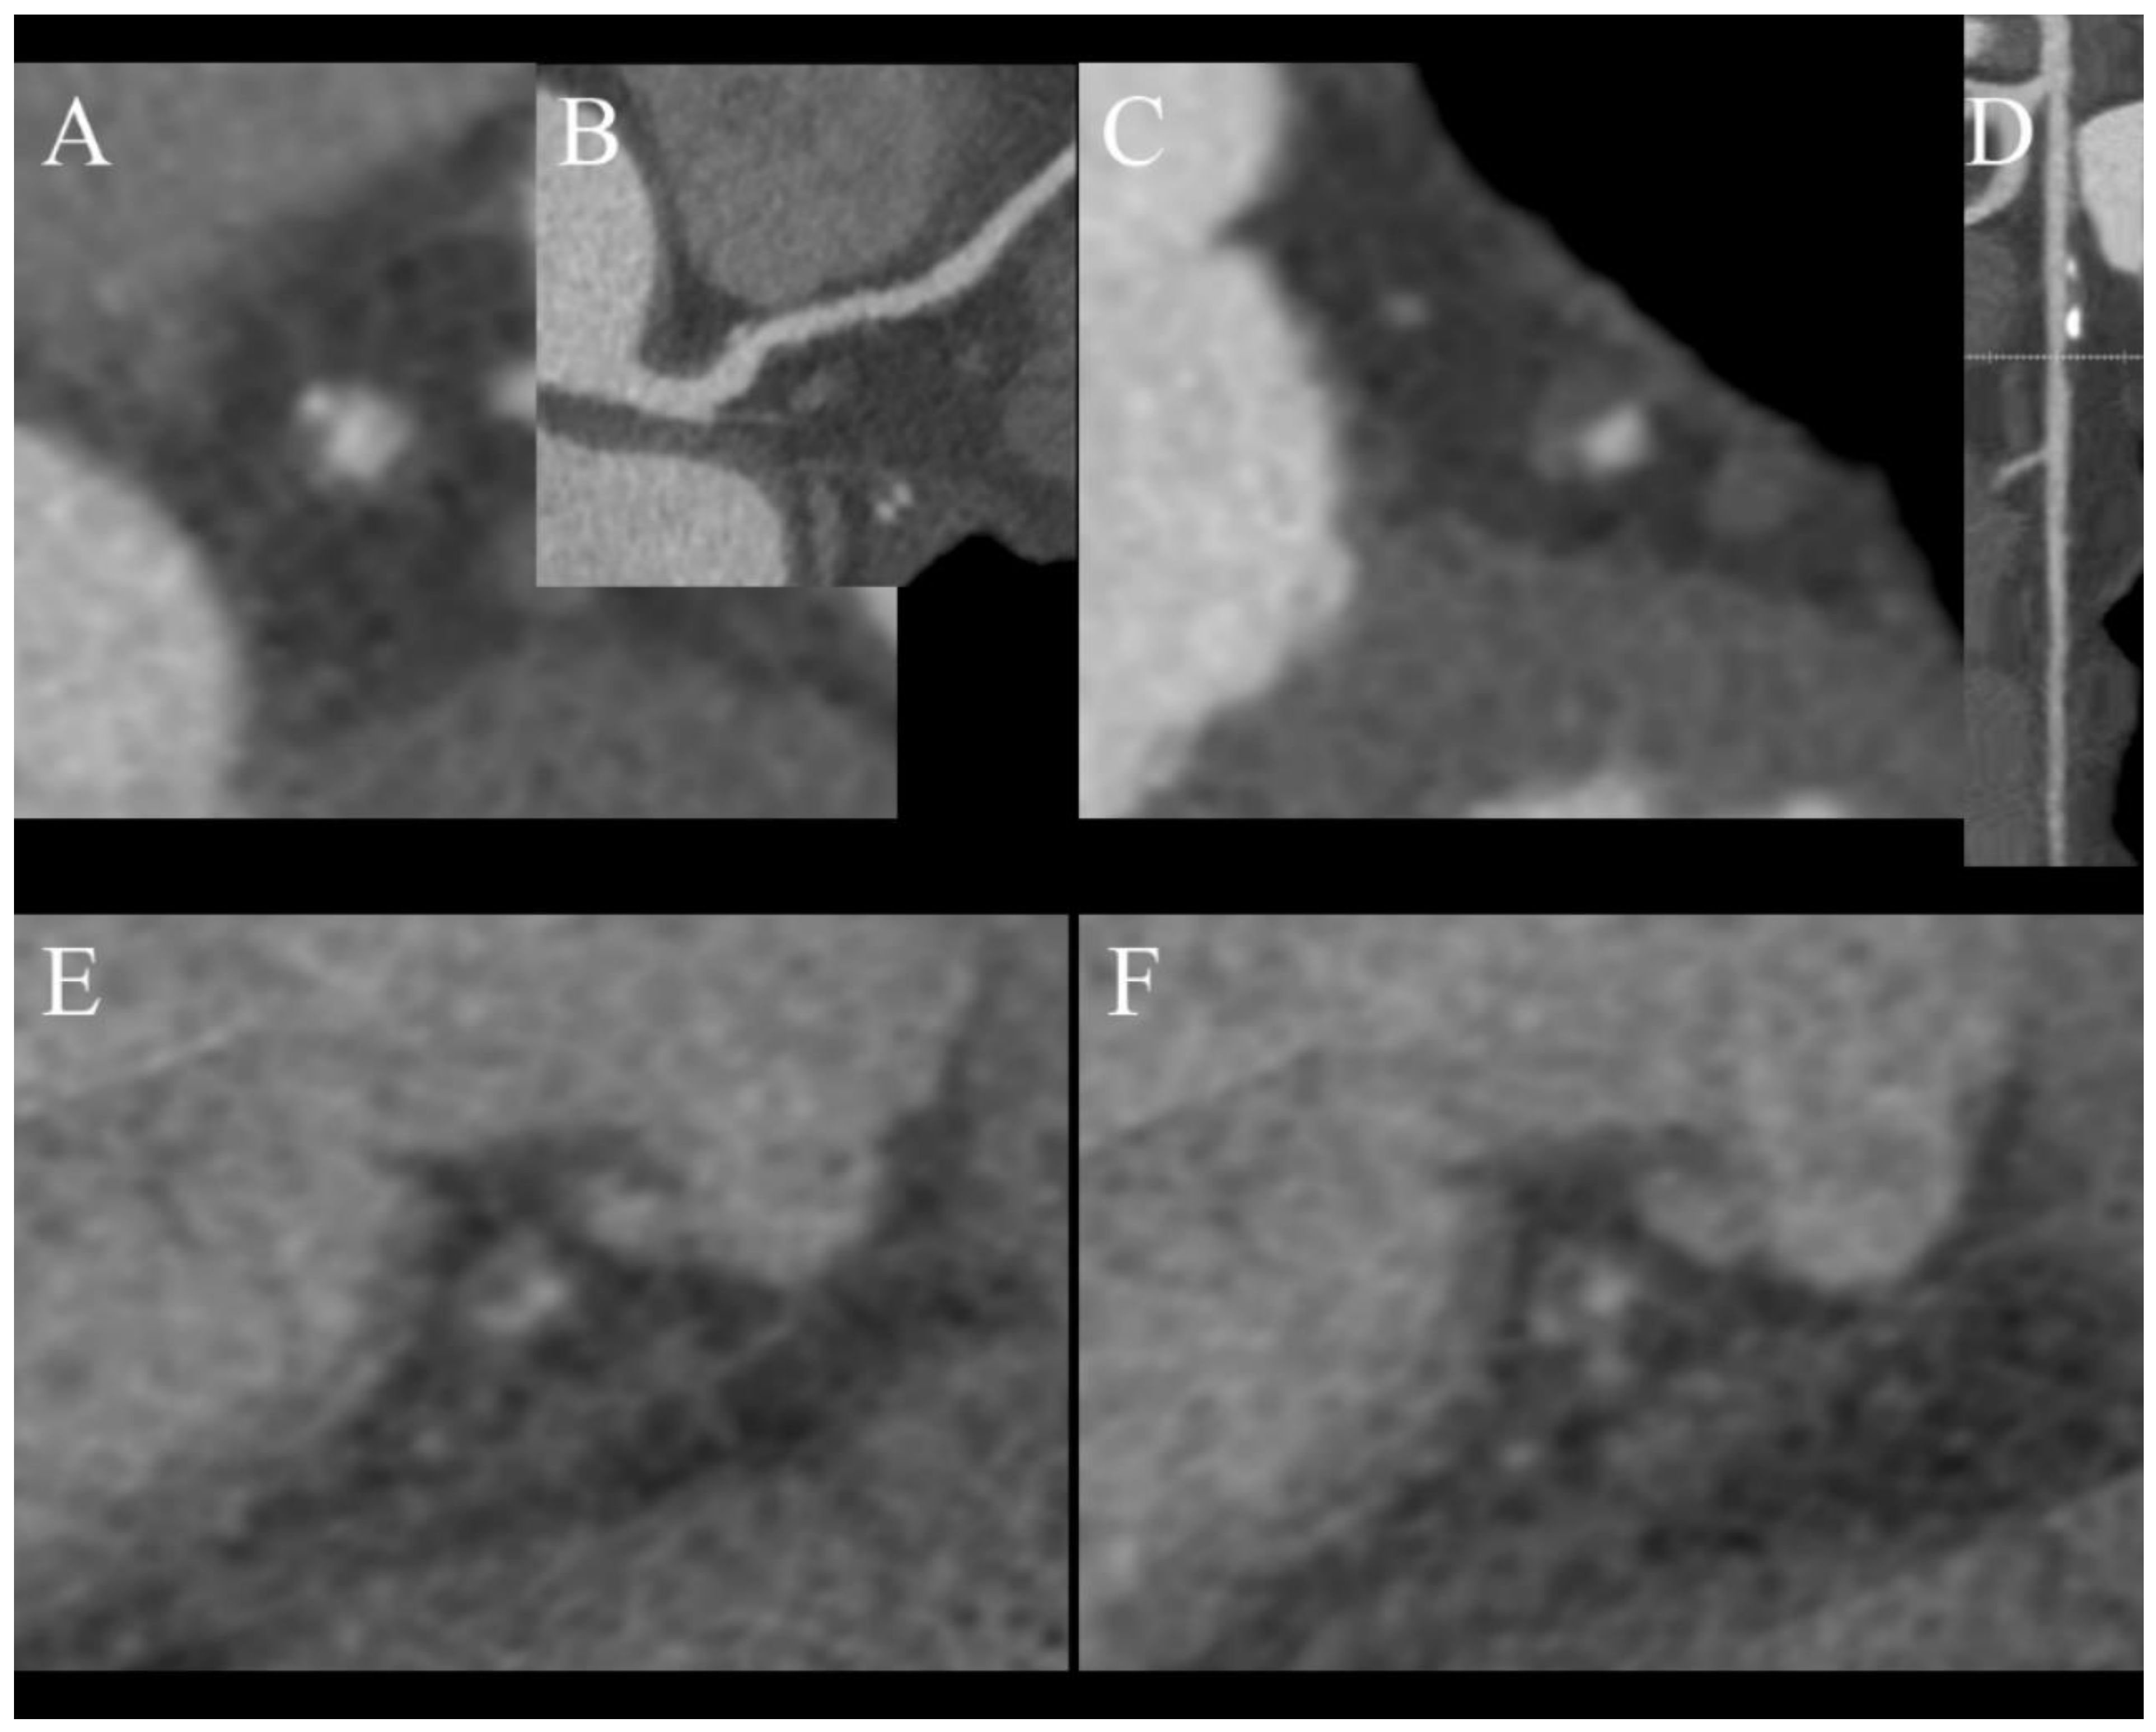

Despite the constant development of CT scanners, invasive coronarography still has much better spatial and temporal resolutions then any CT scanner, but it cannot provide any information about plaque composition. These data are only obtainable by performing intravascular ultrasound (IVUS), which is not widely available. This information is very important because it is proven that plaques with tiny fibrous cups or a large necrotic core are prone to rupture and cause myocardial infarction, which makes them very dangerous. SECT can provide limited information about plaque composition by evaluating its density. DECT can offer much more than just plaque density, by analyzing its atomic number [37,38,39]. Several studies have proved that is possible to assess the composition of soft plaque using DECT and more accurately detect venerable ones, which can lead to more intensive and potentially beneficial treatment for patients [37,40,41]. There are some characteristic features of venerable plaques in CT:

- Spotty calcification (Figure 4A,B);

Figure 4. Features of venerable plaques. (A,B)—spotty calcification—calcification smaller than 3 mm and less than 150% lumen diameter (A)—short axis view, (B)—curved MPR of the vessel; (C,D)—positive wall remodeling—outer diameter of involved section of the vessel at least 110% of non-involved part of vessel; (E,F)—both plaques are noncalcified and low density (<30 HU) corresponding to cholesterol reach core, (F)—napkin ring sign—hyperdense outer part of noncalcified plaque. - Positive remodeling (Figure 4C,D);

- Low density core (Figure 4E,F);

- Napkin ring sign (Figure 4F).

A study by Nakajima et al. determined that using a value of 9.3 as the effective atomic number has 90% sensitivity in distinguishing soft and fibrous plaques, while density with a cutoff value of 55 HU only has 62% sensitivity. A limitation of this study is that it had a small population of just 18 patients [42]. In summary, plaque characterization in DECT has still not been fully researched and requires further investigation, but combining information regarding the effective atomic number with CT features of unstable plaques (Figure 3) can help to determine the nature of atherosclerotic changes in examined vessels [24]. We do not use DECT to characterize plaques in daily practice and rely on CT futures of venerability, which were mentioned earlier.